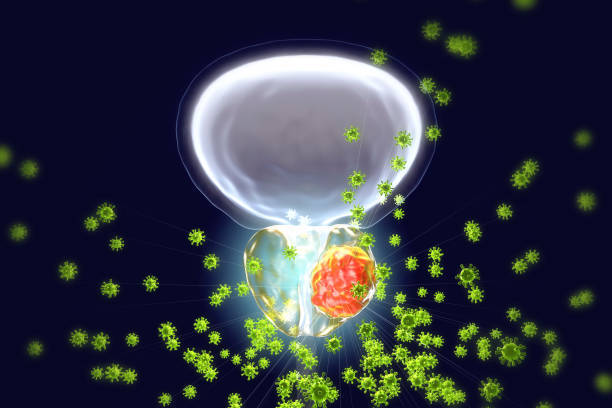

The prostate is a gland located underneath the bladder, in front of the rectum. It plays an important role in the part of the male reproductive system that produces fluids that carry sperm.

Surgery for partial or complete removal of the prostate is called a prostatectomy. The most common causes for prostate surgery are prostate cancer and an enlarged prostate, or benign prostatic hyperplasia (BPH).

The goal of prostate surgery also depends on your condition. For example, the goal of prostate cancer surgery is to remove cancerous tissue. The goal of BPH surgery is to remove prostate tissue and restore the normal flow of urine.